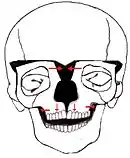

Box Osteotomy Facial Bipartition

Facial Bipartition